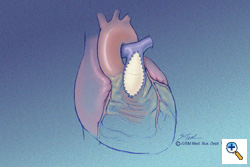

PTFE Outflow Tract Patch

The PTFE outflow tract patch forms a roof over the monocusp. This patch is sutured to the main pulmonary artery and to the ventriculotomy edge and in effect reinforces the suture line of the monocusp itself to the ventriculotomy opening. The dotted line in the mid-portion of this illustration shows the location of the monocusp within the PTFE outflow tract patch. This patch is also sutured in place using running 6-0 PTFE suture. The patch is constructed with 0.4-mm thickness PTFE cardiovascular patch in an elongated teardrop configuration.

The PTFE outflow tract patch forms a roof over the monocusp. This patch is sutured to the main pulmonary artery and to the ventriculotomy edge and in effect reinforces the suture line of the monocusp itself to the ventriculotomy opening. The dotted line in the mid-portion of this illustration shows the location of the monocusp within the PTFE outflow tract patch. This patch is also sutured in place using running 6-0 PTFE suture. The patch is constructed with 0.4-mm thickness PTFE cardiovascular patch in an elongated teardrop configuration.

Monocusp Function

The functional characteristics of the monocusp are demonstrated here. The illustration on the left shows the monocusp in diastole. Blood from the pulmonary artery has filled the monocusp and presses it against the septum and remaining posterior pulmonary valve leaflet. This is the coaptation site of the monocusp. In the illustration to the right, the monocusp is in the open position; this would be during systole. The monocusp is flush with the RVOT anterior RV wall and PTFE outflow tract patch. The function of the monocusp can be evaluated intraoperatively with transesophageal echocardiography.

The functional characteristics of the monocusp are demonstrated here. The illustration on the left shows the monocusp in diastole. Blood from the pulmonary artery has filled the monocusp and presses it against the septum and remaining posterior pulmonary valve leaflet. This is the coaptation site of the monocusp. In the illustration to the right, the monocusp is in the open position; this would be during systole. The monocusp is flush with the RVOT anterior RV wall and PTFE outflow tract patch. The function of the monocusp can be evaluated intraoperatively with transesophageal echocardiography.